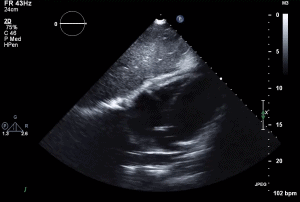

14 RVF A2C LV